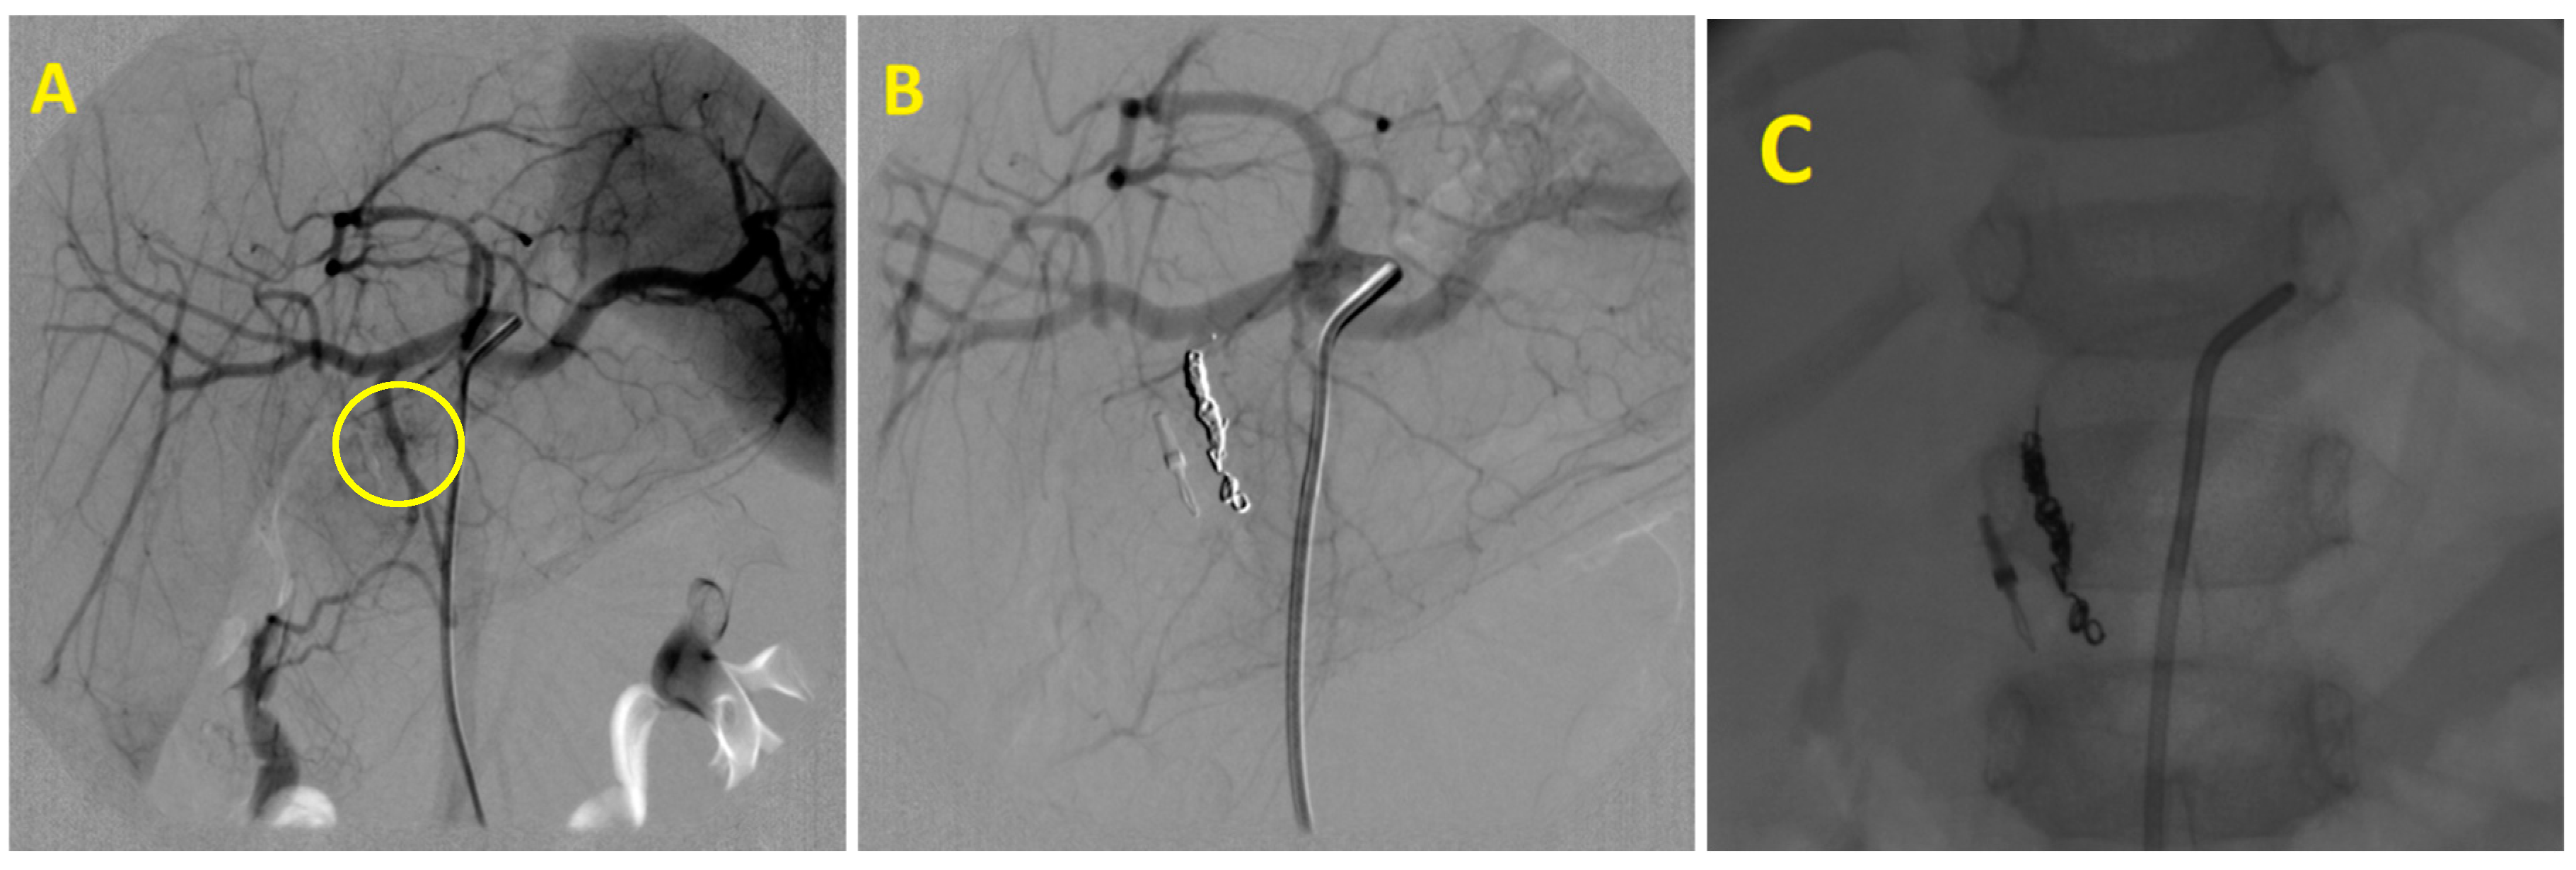

The median time interval between initial clinical manifestations and angiography was 5.5 days (14 h to 22 days). Pathological angiographic findings were confirmed in 24 out of 27 patients (88%). Active bleeding was identified in nine cases, pseudoaneurysms in seven patients (Figure 1), tumor enhancement was found four times, and pathological hypervascularization in the ulcer area was observed in two cases. Both arterioportal fistula and pseudoaneurysm with arteriovenous fistula in the liver were found once each. In three cases, it was not possible to angiographically identify the source of hemorrhage. Despite negative angiographic findings, two of these patients also underwent empirical embolization of the gastroduodenal artery, with continued bleeding from the duodenal ulcer, which was initially treated endoscopically. In total, embolization was performed in 26 patients (96%). The etiology of the hemorrhage, treated arteries, and used embolic materials are shown in Table 2.

Figure 1. Embolization of superior anterior pancreaticoduodenal artery pseudoaneurysm: (A)—Superior anterior pancreaticoduodenal artery pseudoaneurysm after pancreatic pseudocyst endoscopic treatment. (B)—Embolic agent–coils. (C)—Final angiogram confirming pseudoaneurysm occlusion.